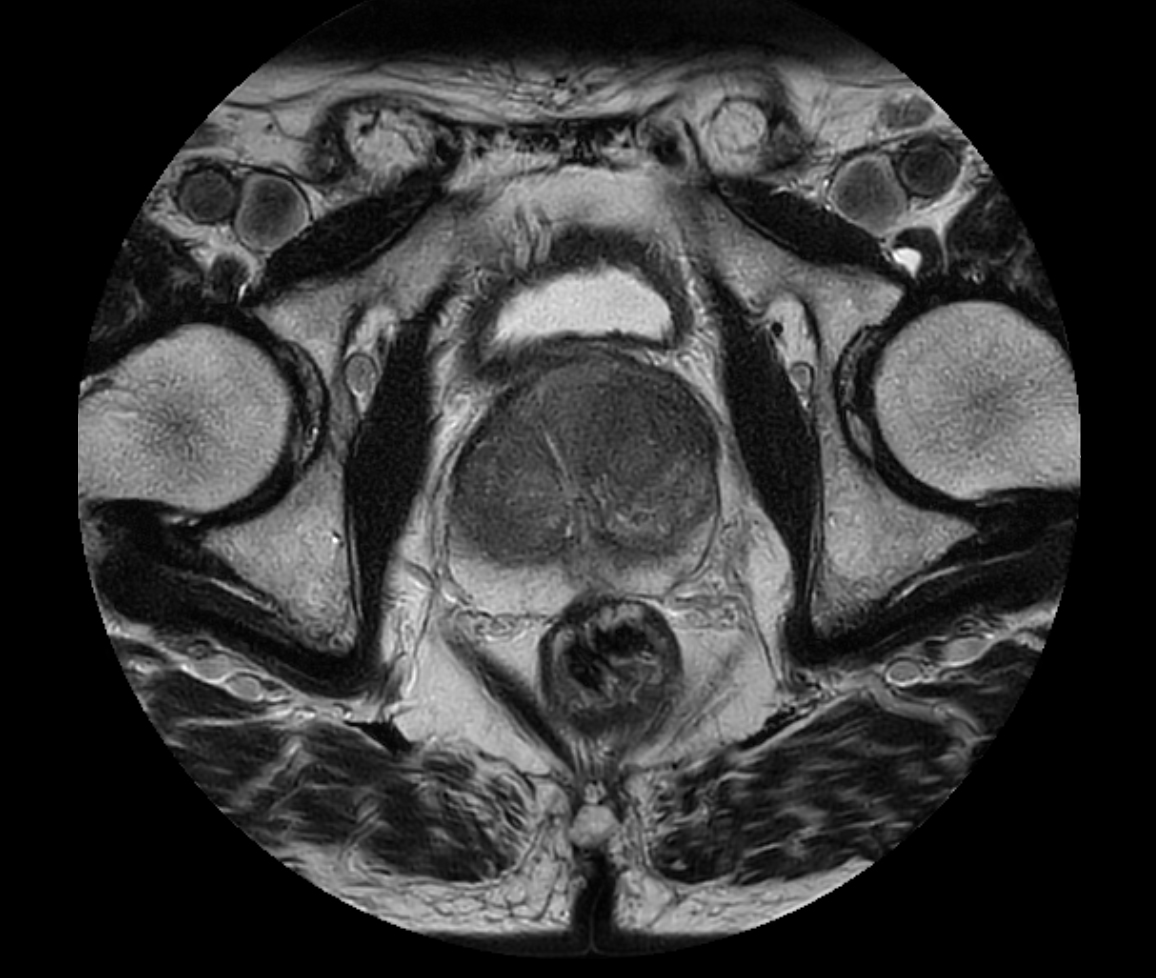

Axial T2w TSE FatSat

Axial T2w TSE - MultiVane XD